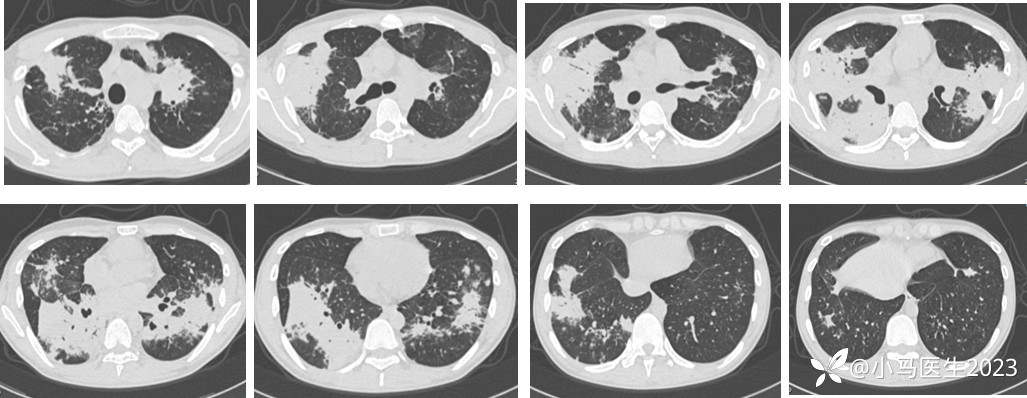

第一阶段治疗

患者要求经验性治疗,予甲泼尼龙40mg qd×7天,03-15复查

胸部CT无明显变化,予口服甲泼尼龙40mg带药出院

03-29复查胸部CT进展

胸部CT对比

胸部CT表现

吸入/淋巴道传播

下肺分布优势

累及双肺,多叶段分布

实变、磨玻璃、粟粒细节、网格结节等

胸膜增厚,胸腔积液

与结核极易混淆!